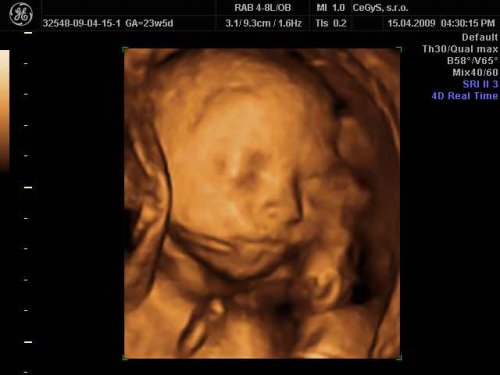

Čakáme bábo